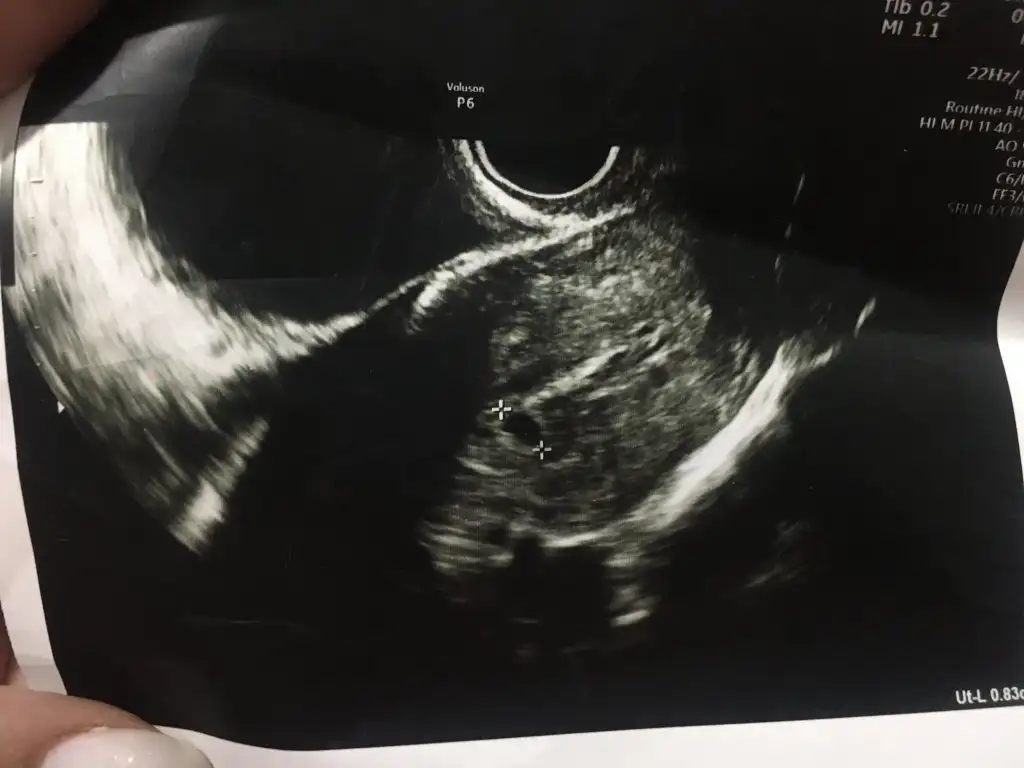

kesenin içi boş görünüyor 8mm haftasına göre boyutu da küçük sanırım ama doktora sorduğumda küçük demedi 1 hafta içindeki gelişimi önemli dedi belki de stres yaptırmamak için öyle dedi bilmiyorum. 5+2 den bu ultrason

doktorum şu an betanın artışa geçmesinin bir gelişimin olduğunu göstergesi diyor. cuma günü tekrar betaya bakacak. düşüyorsa kürtaj randevusu verecek cuma günü ama tekrar artarsa sanırım biraz daha beklicez. bugün kürtaj için randevu verecekti fakat böyle olunca progestrona devam et gözlemleyelim betayı ve kese boyutunu dedi.